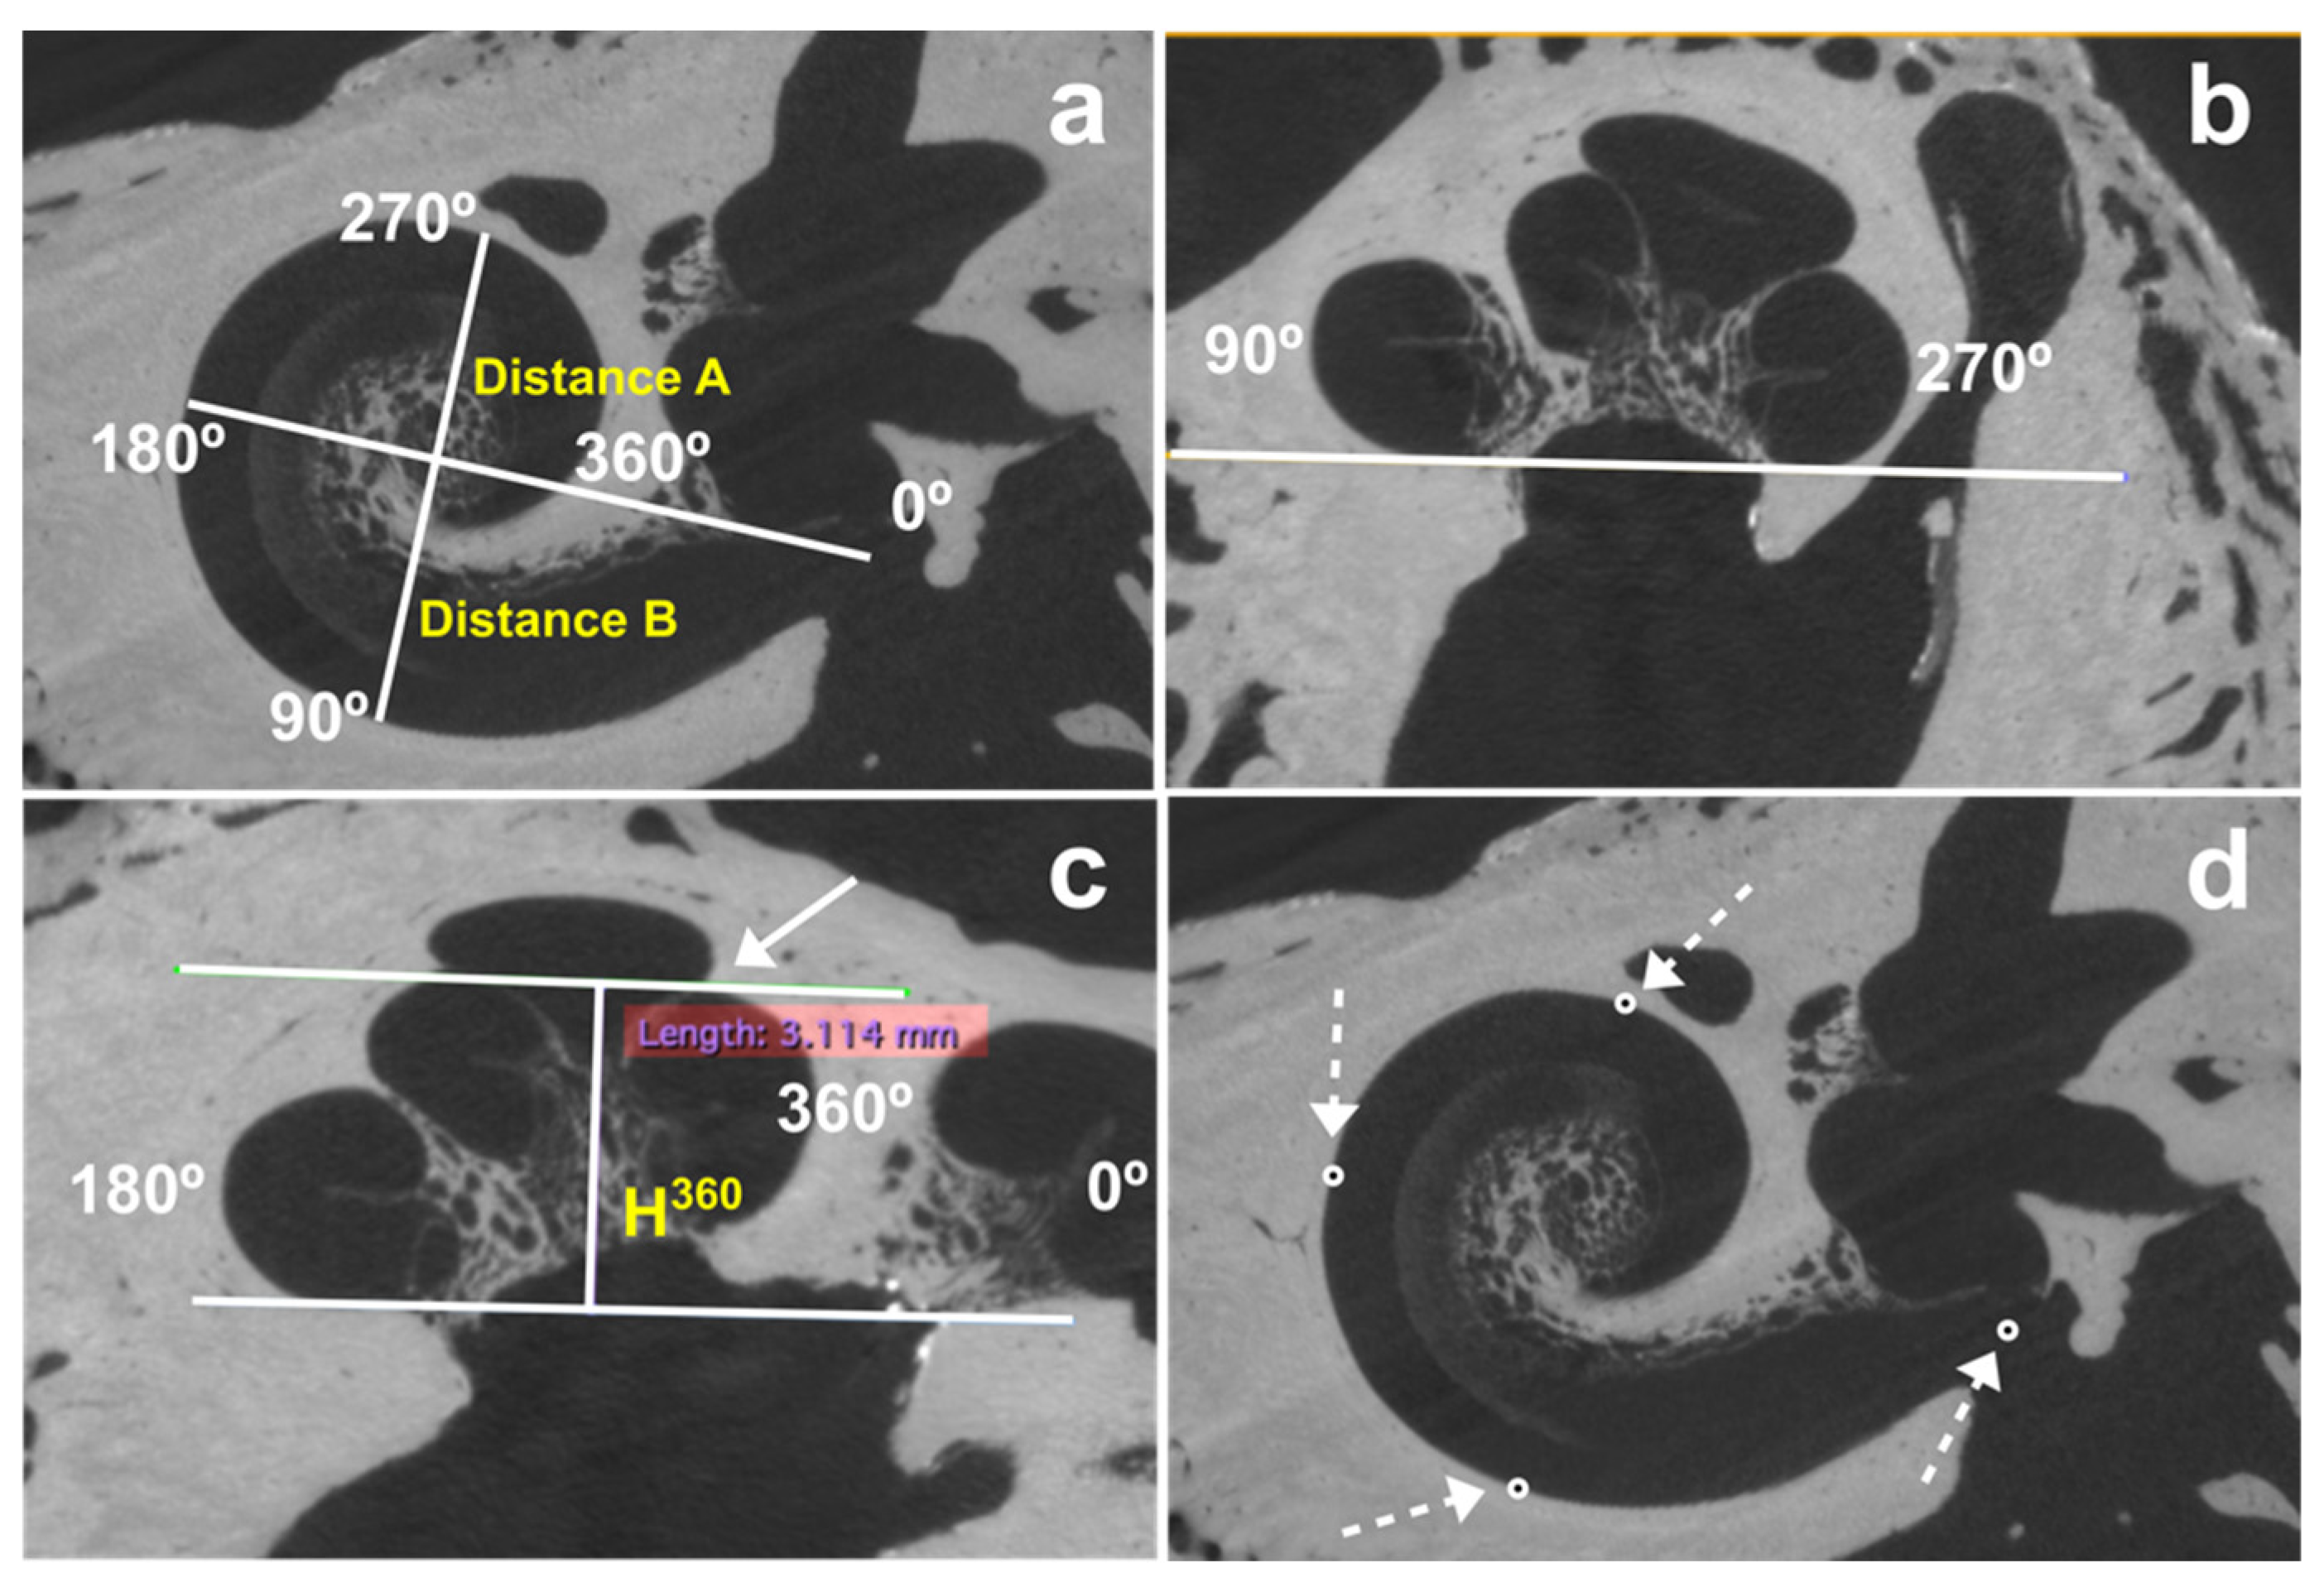

2.2.1. Determination of Cochlea Dimensions

- Distance A (A) between the center of the round window and lateral wall at 180°;

- Distance B (B) between the lateral wall at 90° and 270°;

- The height at 360° (H360), measured from the base of the cochlea to the highest point of the cochlear turn at 360°.